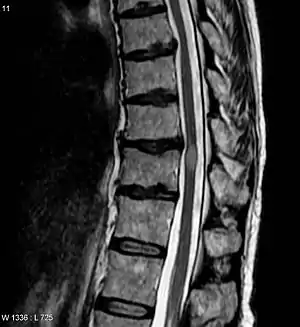

A proposed special clinical presentation is the "longitudinally extensive transverse myelitis" (LETM), which is defined as a TM with a spinal cord lesion that extends over three or more vertebral segments.[17] The causes of LETM are also heterogeneous[18] and the presence of MOG auto-antibodies has been proposed as a diagnostic biomarker.[19]